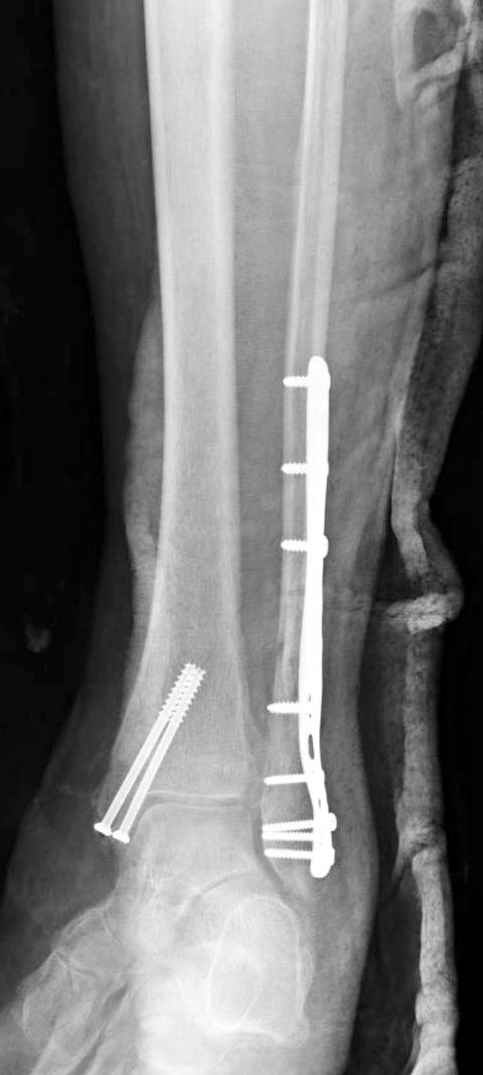

На 4-й неделе убрал спицы, с 7-й недели начал ЛФК, дозированную нагрузку, физиопроцедуры, массаж. Назначил хондропротекторы. Получилось вот что.

Rg-05.JPG

Удалены спицы, а гипса не было? 3-х лодыжечный перелом фиксировать 4 недели недостаточно. Что и подтверждается на последнем снимке - есть тенденция к подвывиху кнаружи, кзади... Что будет дальше, когда пациент начнет давать полную нагрузку?

Малоберцовая выглядит коротковатой. Профиль как-то мутный. Вообще, неплохо было бы сделать снимки в сравнении со здоровой.

Пока я был в интернатуре, предпочитали осуществлять стабильный остеосинтез с ранней функцией. См. приложения и полнотекстный вариант

статьи.